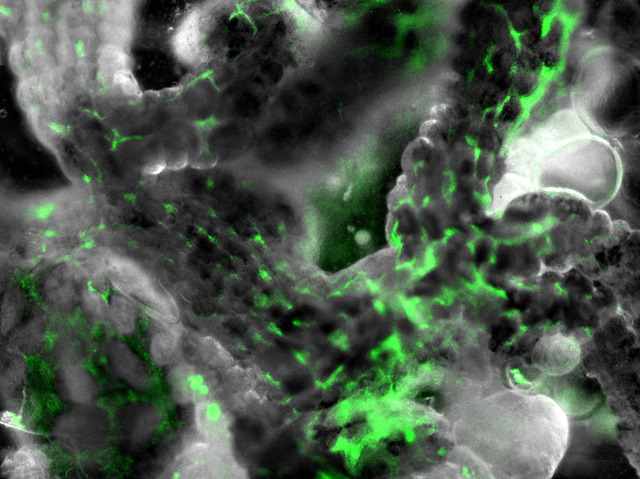

With the approaching summer weather, blood-sucking ticks are gearing up in forests and heaths to prey on unsuspecting ramblers and dog-walkers. An estimated 0.5% of ticks in England and Wales are infected with the Lyme disease-causing bacterium Borrelia burgdorferi, pictured here (in green) deep inside the gut of a tick. The corkscrew-shaped bacterium was discovered thirty years ago by Willy Burgdorfer when he noticed movements inside the tissue of dissected ticks. Britain has until now been spared the epidemic levels of Borrelia infection seen in parts of continental Europe and North America, but climate change and increased travel may have introduced infected non-native ticks. Cases of Lyme’s disease have trebled from 2003 to 2010 (to 905). Underreporting due to lack of awareness could mean the real figure is closer to 3,000.